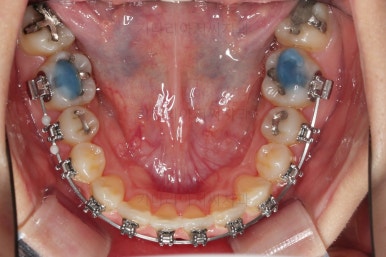

장치를 구성합니다.

이번 환자분은 윗니는 세라믹, 아랫니는 메탈 장치를 선택하셨는데요.

둘 다 물론 자가결찰 장치였고요.

동일한 제품의 장치이므로 혼용해서 쓰는게 가능합니다.

많이 보이는 부분은 세라믹, 잘 안보인다고 여겨지시는 부분은 메탈로 선택하면서 치료비 측면도 함께 고려한거죠.

장치 부착 직후의 모습인데요.

아랫니는 발치 없이 가지런하게 해주고요.

윗니는 가지런하게 한 뒤 발치공간을 서서히 닫아줍니다.

유치는 크기가 작았기 때문에 생각보다 빨리 공간이 닫히고 있고요.

반대쪽 작은 어금니 부분은 공간이 아직 많이 남은 편이죠.